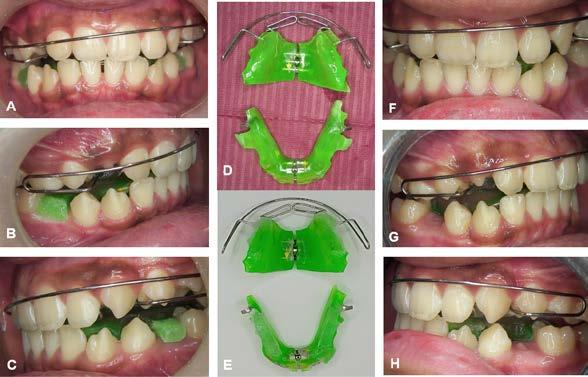

Figura 3. Primer aparto SN1 con almohadillas vestibulares. A. VF con aparato, B. VL derecha C. VL izquierda. D. SN1, vista oclusal (VO). Después de 7 meses del tratamiento se observa los avances obtenidos por el aparato y los ajustes del mismo los cuales observamos en las figuras: E. VO del SN1 7mm de crecimiento transversal, F. VF con aparato, 3G. VL derecha, H. VL izquierda.

Figura 4. Segundo Aparato SN1. A. VF con aparato, B. VL derecha, C. VL izquierda, 3D. SN1, VO. Después de 5 meses del tratamiento se observa los avances obtenidos por el aparato y los ajustes del mismo los cuales observamos en la imagen, E. VO del SN1 5 mm de crecimiento transversal, F. VF con aparato, G. VL derecha, H. VL izquierda.

Figura 5. Tercer aparato PIPS A. VF con aparato, B. VL derecha, C. VL izquierda, D. PIPS VO. Después de 7 meses del tratamiento se observa los avances obtenidos por el aparato y los ajustes del mismo los cuales observamos en la imagen, E. VO del PIPS sin los mantenedores de espacio, 5. VF con aparato, 5G. VL derecha, 5H. VL izquierda.

Después de 18 meses de tratamiento con ortopedia funcional de los maxilares, podemos hacer una comparativa de los resultados obtenidos.

Al observar las imágenes en el antes y el después podemos concluir que se previenen y se bloquea el avance de la maloclusión dental y esquelética clase II división 2 en el paciente, de esta manera se previenen tratamientos más invasivos y complejos

Figura 6. Fotos intraorales antes y después del tratamiento. A. VF B. VL derecha, C. VL izquierda, después de 18 meses de tratamiento D. VF, E. VL derecha, F. VL izquierda.